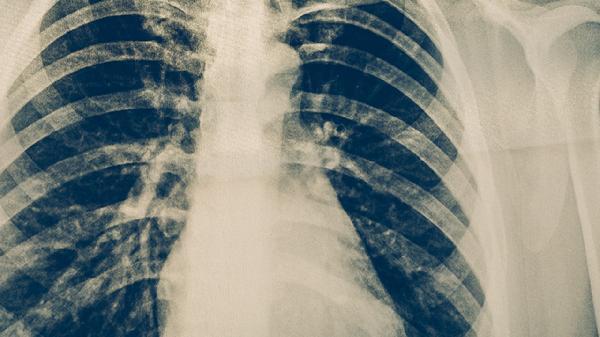

5、其他恶性肿瘤

对结直肠癌、肺癌等也有一定辅助治疗效果。需配合肿瘤类型选择相应治疗方案,如结直肠癌可联合康莱特软胶囊使用。所有用药均需严格遵循医嘱,不可替代主流抗肿瘤治疗。